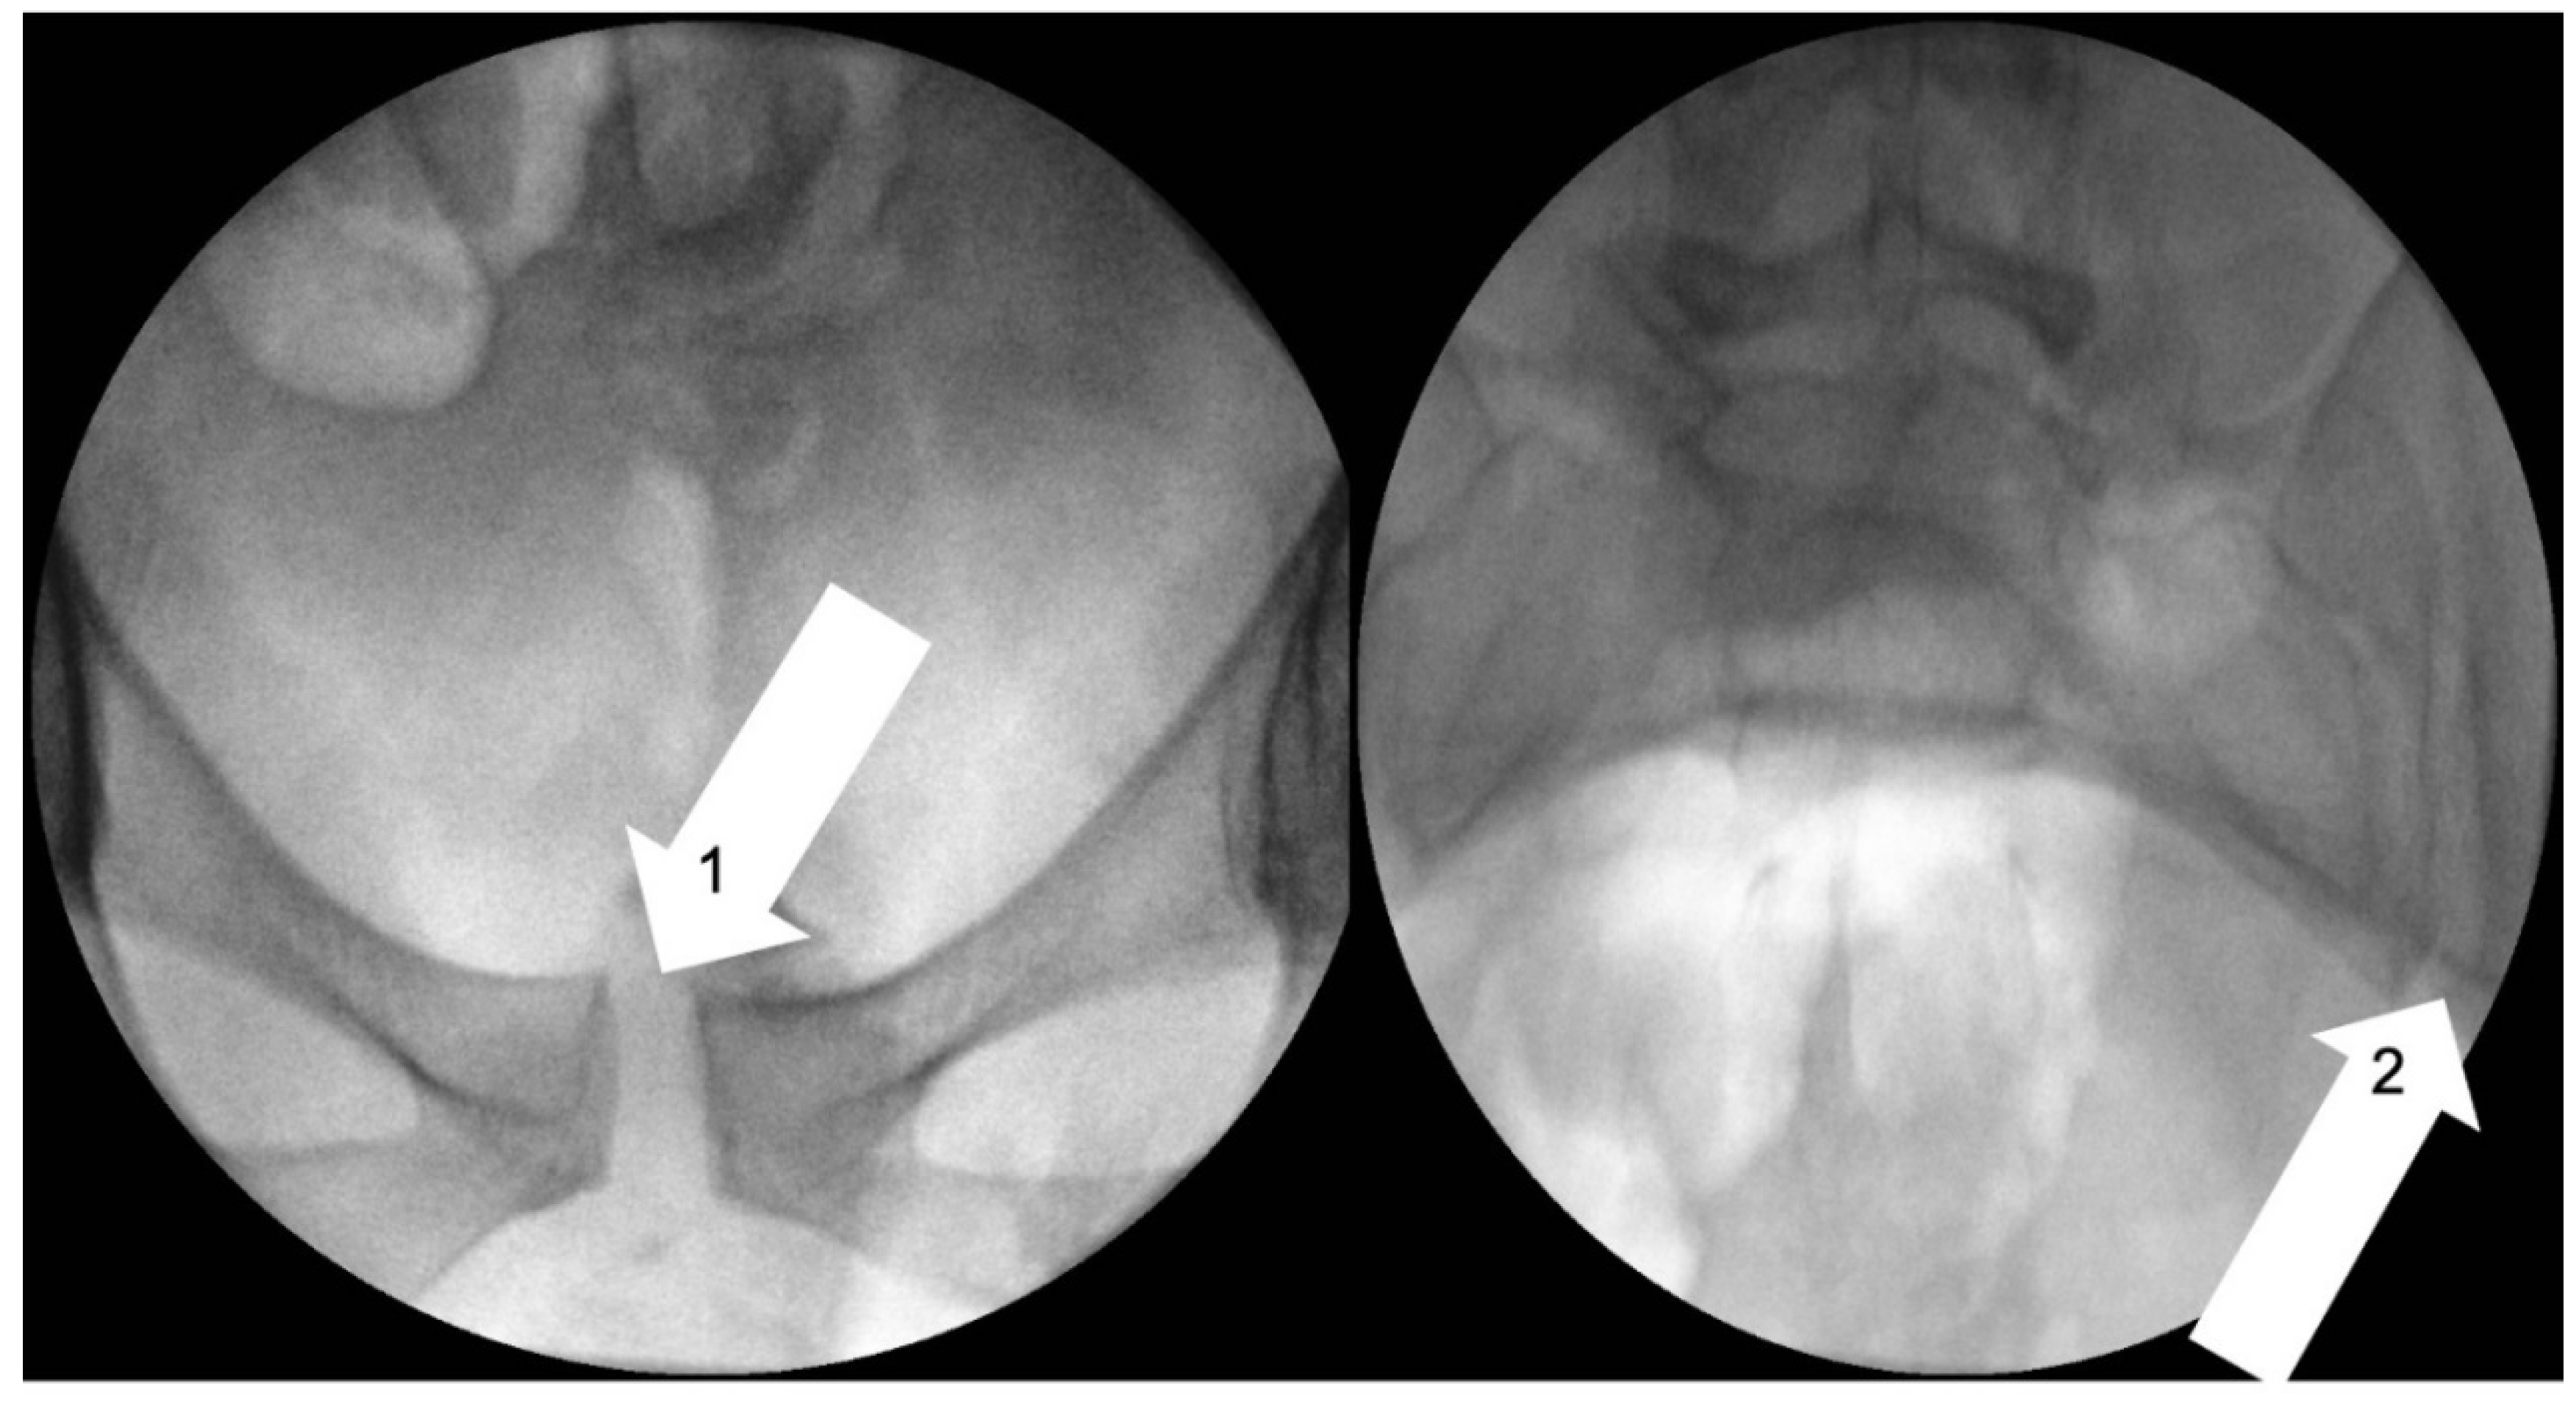

- Garras, D.N.; Carothers, J.T.; Olson, S.A. Single-leg-stance (flamingo) radiographs to assess pelvic instability: How much motion is normal? J. Bone Joint Surg. Am. 2008, 90, 2114–2118. [Google Scholar] [CrossRef] [PubMed]